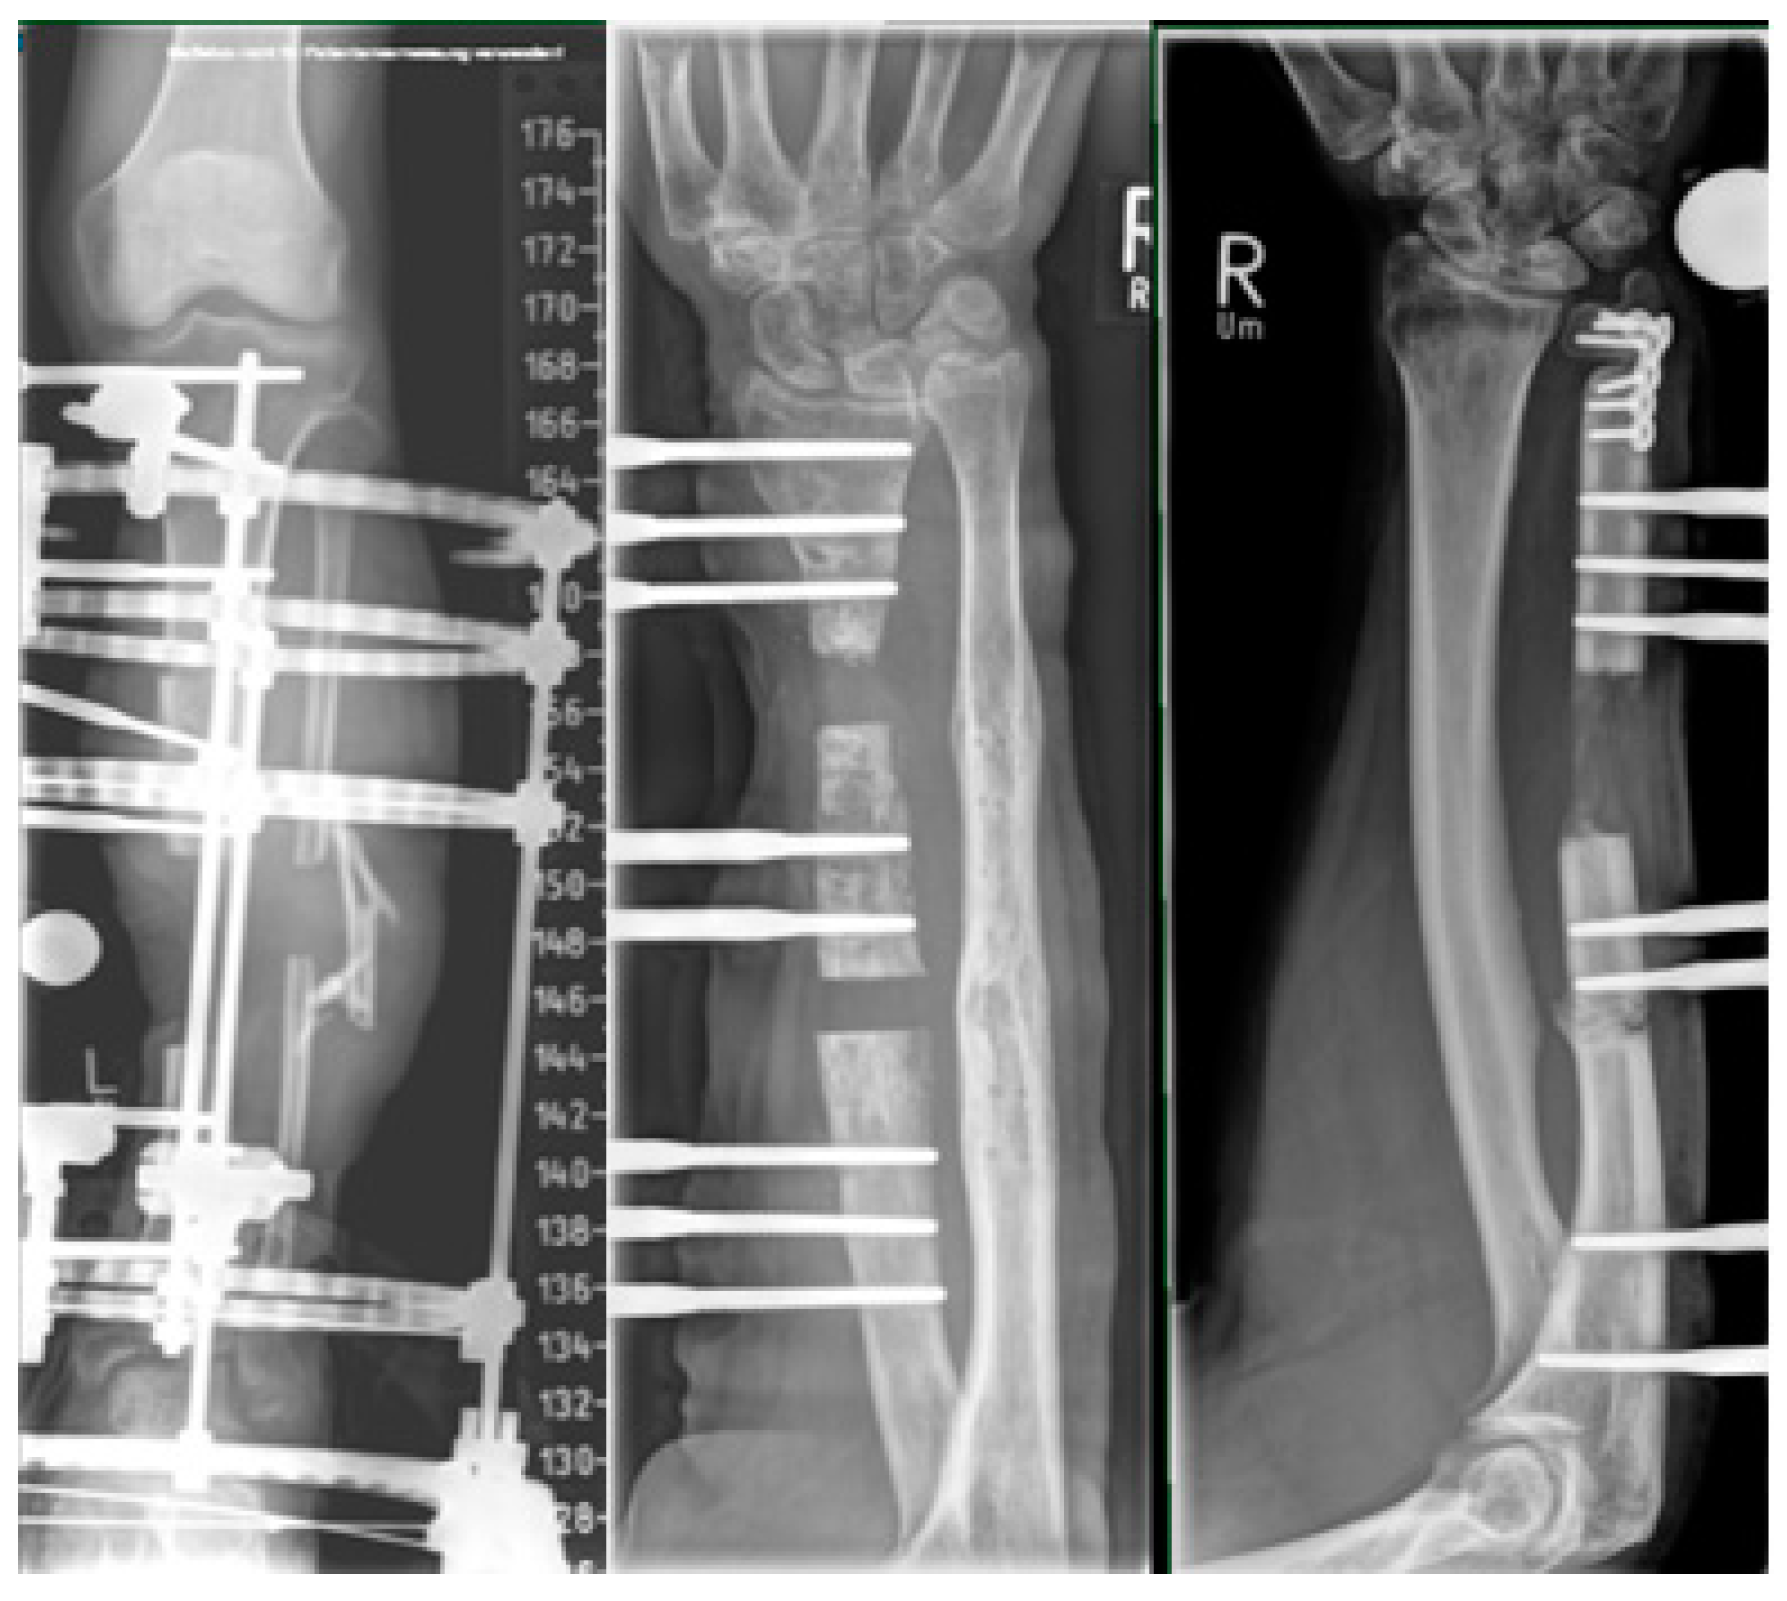

1.2. Hybrid Techniques of Segmental Bone Transport

2.4. Plate-Assisted Bone Segment Transport (PABST)

2.5. MagicTube